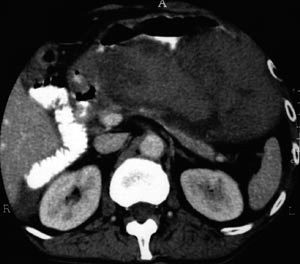

I tillegg til teksten er studiane vurdert systematisk i e-tabell 2 (5, 7) – (10, 12). Det vanlege inklusjonskriteriet i studiane er CT-påviste nekrosar i pancreas (fig 1 – 4) saman med klinisk akutt pankreatitt.